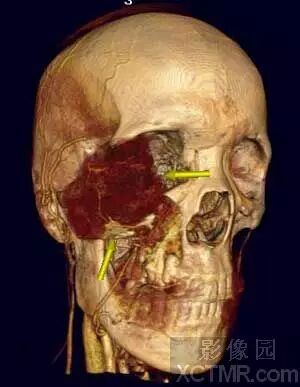

(1)骨骼

VR图像可以立体、直观和清晰地显示正常颅骨、躯干骨和四肢骨的生理性突起(如:棘、粗隆、结节和嵴等)、凹陷(如:窝、沟和压迹等)、空腔(如:腔、窦、管、道、孔等)和膨大(如:头、颈和髁等),以及关节的骨性结构(如:关节头和关节盂等)的形态。对长骨、短骨、扁骨和不规则骨,特别是对显示解剖结构和关系复杂的腕关节、踝关节、肘关节、肩关节、髋关节和脊柱及其附件的骨折,关节脱位,畸形以及骨肿瘤等病变的位置、程度、范围和与周围组织器官的毗邻关系,对骨科和整形外科制定手术方案、预测手术的可能性及评估手术的愈后等都具有很高的临床应用价值。